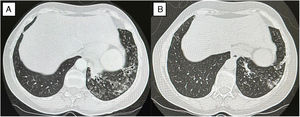

In 2024, after three bronchiectasis exacerbations requiring empirical antibiotics, sputum and bronchoscopy cultures revealed A. xylosoxidans. Two courses of trimethoprim–sulfamethoxazole failed to eradicate the microorganism, and CT imaging revealed progressive cylindrical bronchiectasis with worsening “tree-in-bud” opacities and a Bronchiectasis Severity Index (BSI) score of 7 (Fig. 1A). Nebulized levofloxacin (240mg twice daily, on–off 28-day cycles) was initiated for CBI caused by A. xylosoxidans, in addition to patient's existing maintenance therapy, leading to: marked reduction in daily sputum, resolution of exacerbations, improved lung function and CT findings (Fig. 1B), and sustained microbiological clearance over six months.

(A) Baseline CT scan demonstrating bilateral bronchiectasis in the middle lobe and lingula, accompanied by “tree-in-bud” pattern and endoluminal secretions, with associated volume loss. (B) Follow-up CT after six months of nebulized levofloxacin showing improvement and decreased “tree-in-bud” opacities.